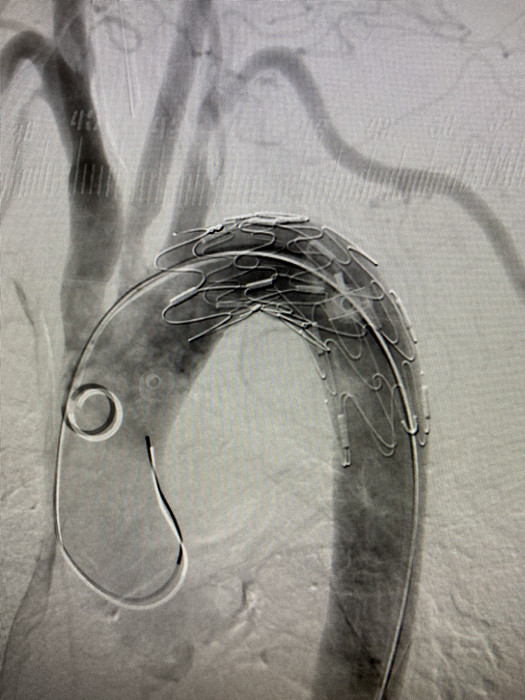

“如果內(nèi)鏡下直接取出異物容易造成患者二次損傷,刺向胸主動(dòng)脈的鴨骨頭最為尖銳,距離主動(dòng)脈壁最近,一旦刺破可引發(fā)致命性大出血?!苯?jīng)消化內(nèi)科、血管外科、心胸外科、放射科、麻醉科等科室緊急會(huì)診,決定為劉奶奶先行胸主動(dòng)脈支架術(shù),后在內(nèi)鏡下行食管異物取出術(shù)。

凌晨4點(diǎn),血管外科副主任醫(yī)師程國(guó)兵,主治醫(yī)師李曉陽(yáng),為劉奶奶進(jìn)行了胸主動(dòng)脈支架植入手術(shù),歷經(jīng)1小時(shí),手術(shù)順利結(jié)束。